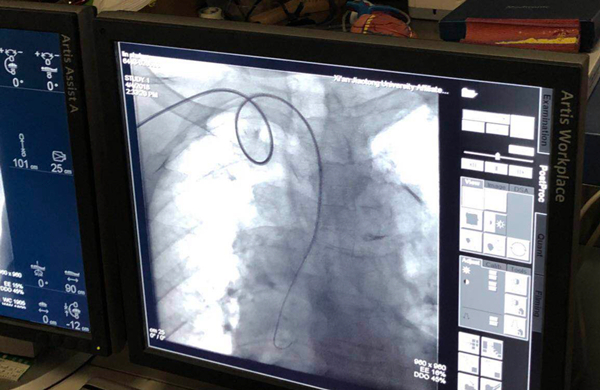

4月4日,在干二病区金爱萍副主任医师、张倩蓉主治医师、李蔚护士等人陪同下,由我院心内科邓捷主任医师、王新宏主治医师、刘昕主治医师等介入团队为林女士在局麻下行冠状动脉造影术,造影显示左右冠脉走形区动脉迂曲,导丝通过困难,血管呈弥漫性钙化,三支血管狭窄最重约60-70%,前向血流TIMIⅢ级,遂撤出导丝,结束手术,术后安返病房。

这是我科首例85岁以上高龄患者实施介入手术检查,在干二病区介入手术史上具有极其重要的意义。为干二病区高龄冠心病患者的进一步明确诊治奠定了基础。